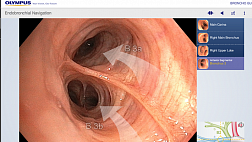

На рисунках 3-4 представлен случай неоперабельного рака поджелудочной железы с поражением нижней трети холедоха и механической желтухой. На первом снимке в область опухолевой стриктуры введен баллон-дилататор, на втором виден установленный стент.

Наш опыт в эндоскопическом стентировании при холангиокарциноме менее оптимистичен, наиболее часто приходится сталкиваться с запущенными формами заболевания (например, тотальном поражении под печеночных желчевыводящих путей), когда необходимо установка стента в правый или левый печеночный проток, что не всегда технически возможно. Пример успешного стентирования показан на рис. 6.